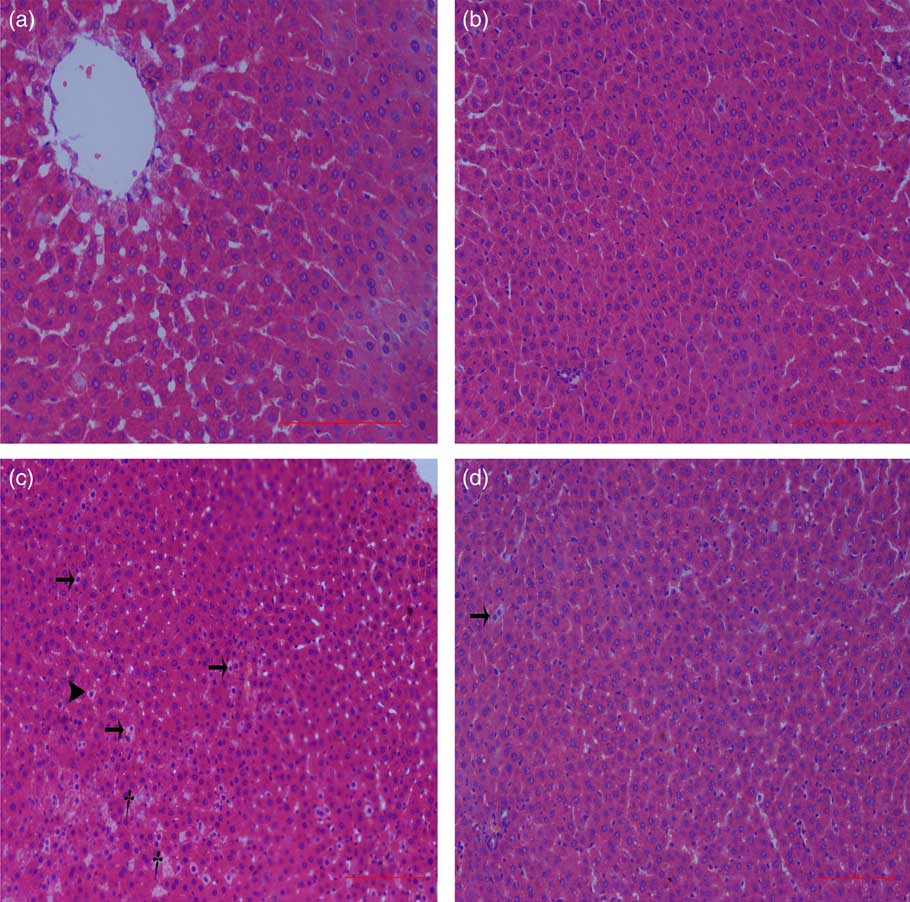

Liver histological changes

Normal histologic structures were observed in the liver of NBW and NC rats (Fig. 4(a) and (b)). In the liver sections of IUGR rats, vacuolisation and cell oedema were prevalent in the hepatocytes, and fat cells showed signs of mild denaturation (Fig. 4(c)). In the IC group, vacuolisation was significantly reduced and no fat cells were observed (Fig. 4(d)).

Fig. 4 Light microscopy of liver tissue in different groups (200× magnification): (a) normal birth weight rats, (b) normal birth weight rats supplemented with curcumin, (c) intra-uterine growth retardation rats and (d) intra-uterine growth retardation rats supplemented with curcumin. Haematoxylin–eosin, scale bar=100 μm. † Vacuole; ![]() , fat cell;

, fat cell; ![]() , cellular oedema.

, cellular oedema.